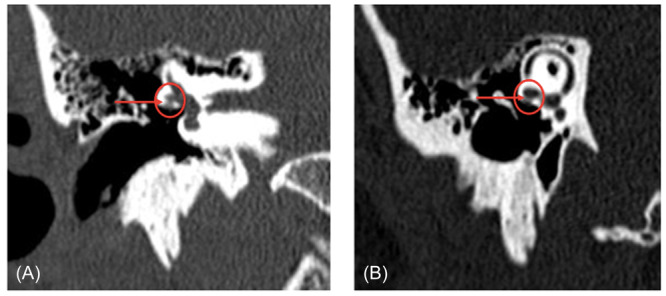

Methods: We measured the bony partition thickness between the FC-LSCC in human temporal bone otopathological specimens and CT scans. The clinical study involved a series of reviews of patients with FC-LSCC, presenting clinical data and CT images.

Results: The average thickness of the bony partition measured via CT was 0.6 mm ± 0.2 mm, whereas in otopathological specimens it was 0.56 mm ± 0.17 mm. We identified 34 patients with FC-LSCC dehiscence. The most frequently reported symptoms were hearing loss (44%), dizziness/vertigo (44%), and tinnitus (41%). Of the patients, 15 (44%) had more than 1 site of bone dehiscence and 21 (62%) had bilateral FC-LSCC dehiscence. We then identified 36 patients in whom only FC-LSCC dehiscences were found and provided characteristics for this population.